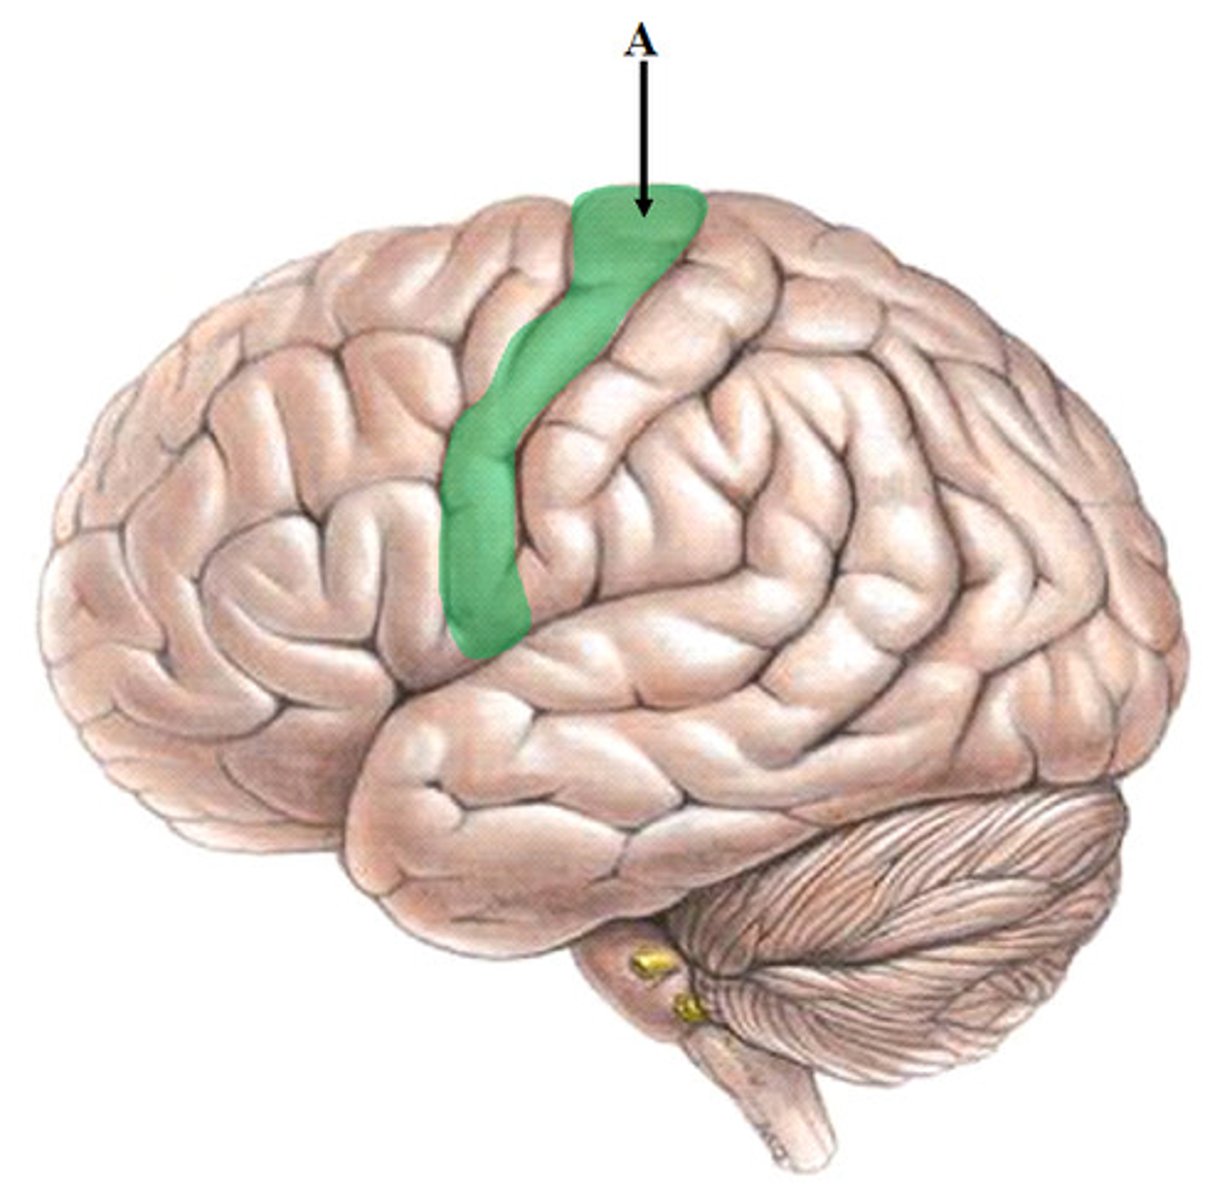

Precentral Gyrus

Postcentral Gyrus

Frontal Lobe

Parietal Lobe